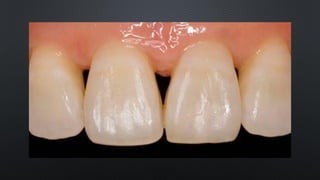

RELAÇÃO INTERDENTAL

LOCALIZAÇÃO DO PONTO DE CONTATO:

- ENTRE OS 1/3 MÉDIO E INCISAL/OCLUSAL

- ENTRE OS 1/3 MÉDIO E VESTIBULAR

SULCO INTERDENTAL: LOCALIZADO

INCISAL/OCLUSALMENTE AO PONTO DE CONTATO

ESPAÇO INTERDENTAL: LOCALIZADO CERVICALMENTE AO

PONTO DE CONTATO

CONTATO PROXIMAL PONTO DECONTATO ÁREA DE CONTATO RELAÇÃO INTERDENTAL

LOCALIZAÇÃO DO PONTODE CONTATO: - ENTRE OS 1/3 MÉDIO E INCISAL/OCLUSAL - ENTRE OS 1/3 MÉDIO E VESTIBULAR RELAÇÃO INTERDENTAL

SULCO INTERDENTAL: LOCALIZADO INCISAL/OCLUSALMENTEAO PONTO DE CONTATO ESPAÇO INTERDENTAL: LOCALIZADO CERVICALMENTE AO PONTO DE CONTATO RELAÇÃO INTERDENTAL